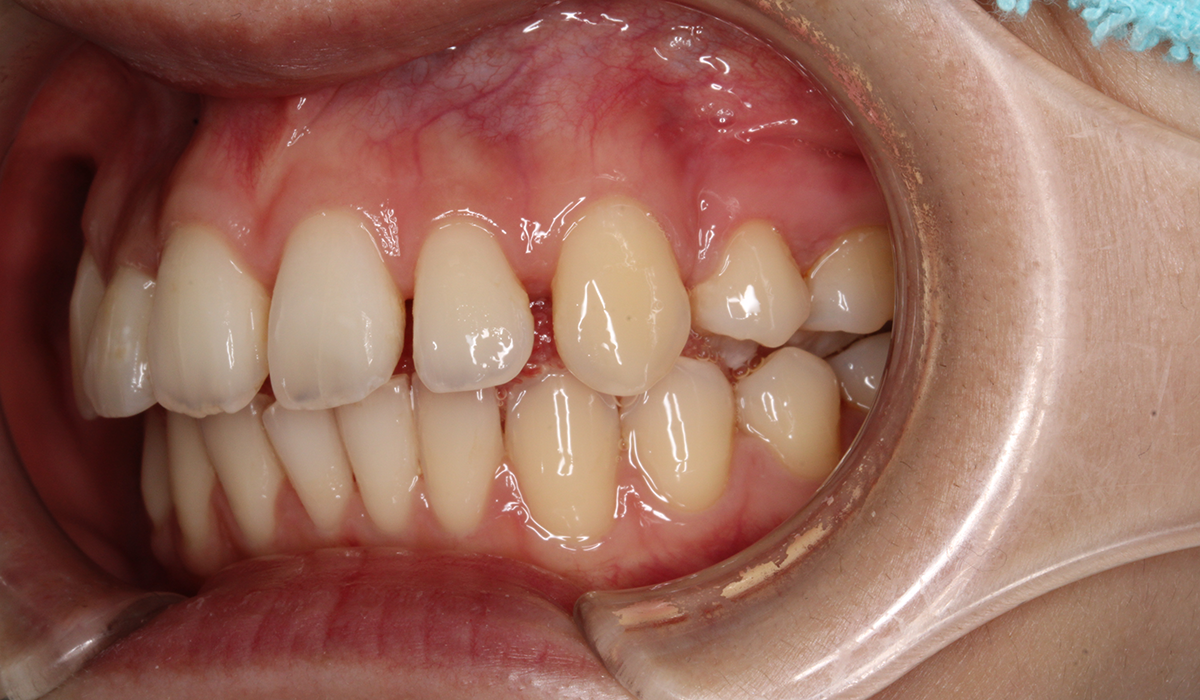

左側

術前